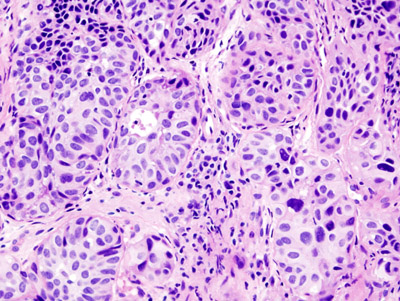

Flat urothelial carcinoma is characterized by the invasion of a high-grade flat tumor and is associated with p53 early mutations.

Papillary urothelial carcinoma initially appears as a low-grade papillary tumor, advances to a high-grade papillary tumor, then invades, and is not linked to early p53 mutations.

Urothelial carcinoma arises via two distinct pathways:

- Flat

- Papillary